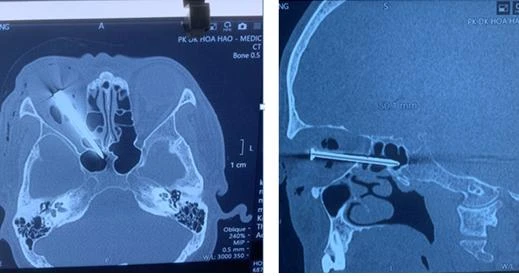

Cây đinh dài 5 cm đâm xuyên mắt phải ông H. Ảnh: BVCC |

Ông H. là phụ hồ. Trong lần giăng dây để đóng cốt pha đổ bê tông, ông H. dùng cây đinh 5 cm cột vào dây nhợ rồi đóng chặt cố định một điểm. Tiếp theo, ông H. dùng sức kéo căng dây nhợ đến vị trí đóng cây đinh thứ hai cũng dài 5 cm làm mốc tiếp theo. Tuy nhiên do đóng không chặt, cây đinh thứ hai bung ra lao vào mắt phải ông H.

Ông H. được sơ cứu và chuyển tới vài BV địa phương. Tại đây, ông H. được hút mủ, chích kháng sinh nhưng tình trạng vẫn không cải thiện. Sau đó, BV địa phương phải múc nội nhãn mắt phải. Cuối cùng, dựa trên kết quả chẩn đoán hình ảnh, BV địa phương ghi nhận ông H. bị dị vật đâm xuyên mắt phải phức tạp nên chuyển đến BV Nhân dân 115 TP.HCM.

Tại đây, các BS nhận định dị vật là cây đinh dài 5 cm xuyên ổ mắt phải qua xoang sàng, xoang bướm. Chưa hết, đầu nhọn cây đinh đâm cạnh trái khe thần kinh thị mắt phải và nằm gần thành trái xoang bướm phải.